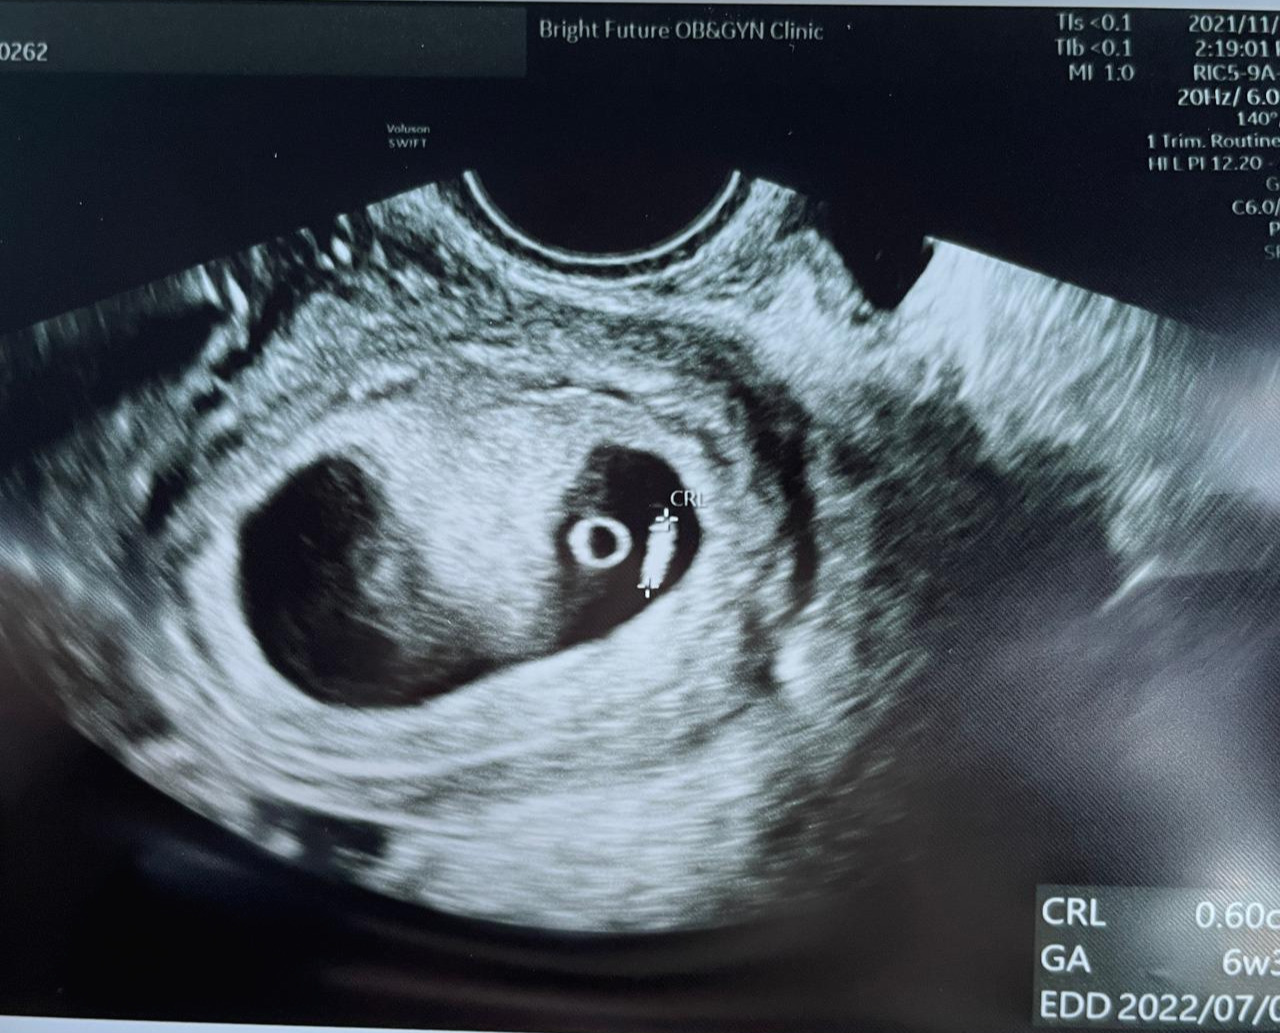

하지만 2주마다 쑥쑥 크는 아기 초음파를 보며, 작게 움직이는 아기의 움직임을 보며 느낀 벅찬 감정은 모든 부정적인 감정을 잊게 해 줬다.

작은 아기집에서 난황과 작은 아기, 손과 발이 생겨서 꼼지락대기까지 성장한 아기의 모습

내 자식이 행복하게 잘 크길 기원하면서 말이다. 아기의 팔다리가 나오는 게 보이자, 집에 돌아가는 길에 단백질이 함유된 요플레와 건강한 샐러드를 사 온 나처럼.

당장 울렁이고 못 먹겠더라도 초음파 속 아기 팔다리가 만들어지고 있는데 건강하게 잘 크도록 지켜주고 싶었기 때문이다. 튼튼하고 무탈하게 잘 크길 바라면서 말이다.